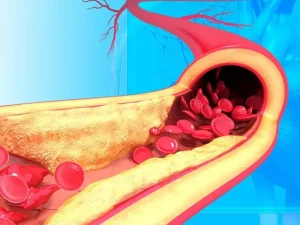

درمان بیماری گرفتگی عروق کرونر بسته به نوع گرفتگی میتواند بدون درد یا عمل باشد و با تغییراتی در سبک زندگی مانند ترک سیگار، داشتن

گرفتگی رگ های قلب میتواند بسیار خطرناک بوده و عوارض جبرانناپذیری را برای بدن بهدنبال داشته باشد. زیرا قلب یکی از پراهمیتترین و حساسترین ارگانهای